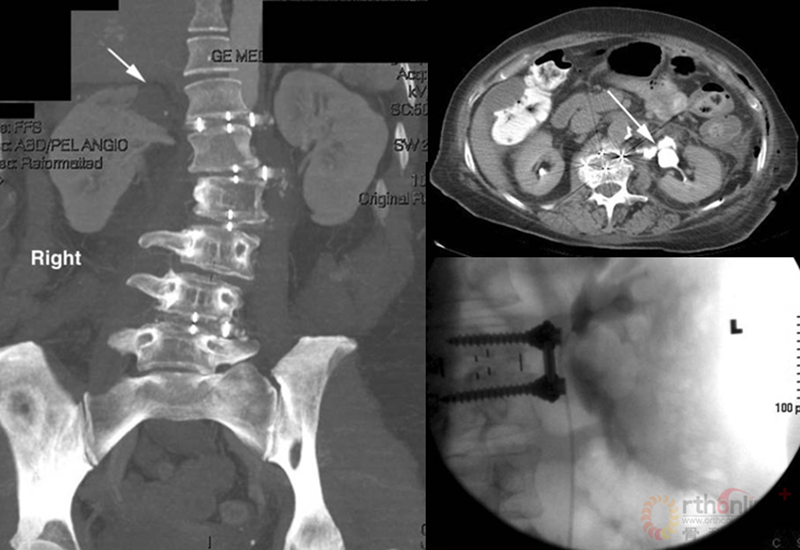

陆军总医院、全军骨科研究所李放教授分析了国内外相关研究,并结合临床经验得出结论:开放手术能够获得更好的矫形和减压效果;微创技术作为脊柱医生手中的新武器,对于一部分畸形较轻的病例,微创技术可以发挥其优势,但要严防特殊并发症;对于畸形严重的病例,微创手术处理存在困难,可谓开放能及微创所不及。他认为,开放和微创技术应该有机结合,重要的是如何去选择适应证,对不同的病例制订个体化方案。